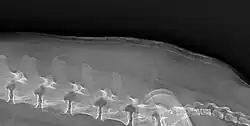

The symptoms of Cushing's in cats is similar to that of dogs.[8] For cats the most common reason for referral resulting in a diagnosis is diabetes mellitus. Abnormal dermatological findings were the most common reason for referral after physical examination in cats.[9] 80% of cats with Cushing's develop diabetes mellitus compared to 10% of dogs.[8] One study of cats found all 30 to have dermatological lesions, 87% to have polyuria or polydipsia, and 70% to have polyphagia.[9] Curling of the tips of the ears may occur.[2]

Cushing's may cause a breakdown of dermal proteins, causing shiny and thin skin, this can lead to secondary infection and is pathognomonic of Cushing's.[2]